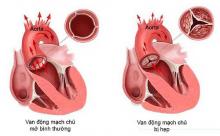

Dị dạng động tĩnh mạch (AVMs) là các đám rối mạch máu bị giãn, trong đó các động mạch dẫn máu trực tiếp vào tĩnh mạch. AVM thường gặp nhất ở chỗ nối của các động mạch não, thường là trong nhu mô não vùng trán - đỉnh, thùy trán, tiểu não bên, hoặc thùy chẩm. AVM cũng có thể gặp ở màng cứng.

Dị dạng động-tĩnh mạch não (AVM) là những tổn thương mạch máu hiếm gặp có thể biểu hiện bằng xuất huyết nội sọ tự phát, co giật hoặc đau đầu, điển hình ở người trẻ tuổi.